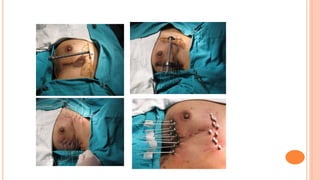

Breast

⚫Indications: Boost after BCS & EBRT

⚫Postoperative interstitial irradiation alone of

the primary tumor site after BCS in selected

low risk T1 and small T2N0 (PBI)

⚫Chest wall recurrences

As sole modality As Boost to EBRT

Patient choice: cannot come for 5-6 wks treatment :

 Distance

 Lack of time

Close, positive or unknown margins

Elderly, frail, poor health patient EIC

Large breasts: unacceptable toxicity Younger patients

Deep tumour in large breast

Irregularly thick target vol.

 T.V.: Primary Tumor site + 2-3 cm margin

 Dose: As Boost: 10-20 Gy LDR

 AS PBI: 45-50 Gy in 4-5 days LDR (30-70 cGy/hour)

⚫ 34 Gy/10#, 2# per day HDR

 Technique:

⚫ Localization of PTV: Surgical clips (at least 6)

 USG, CT or MRI localization, Intraop USG

⚫ During primary surgery

⚫ Guide needle technique or

⚫ Plastic tube technique using Template

 Double plane implant

 Skin to source distance: Minimum 5 mm